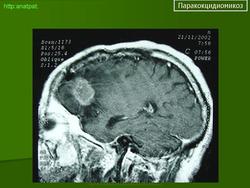

ГМ. Паракокцидиомикоз. +

Паракокцидиомикоз.

Множественные "узловые образования" имитирующие метастазы.